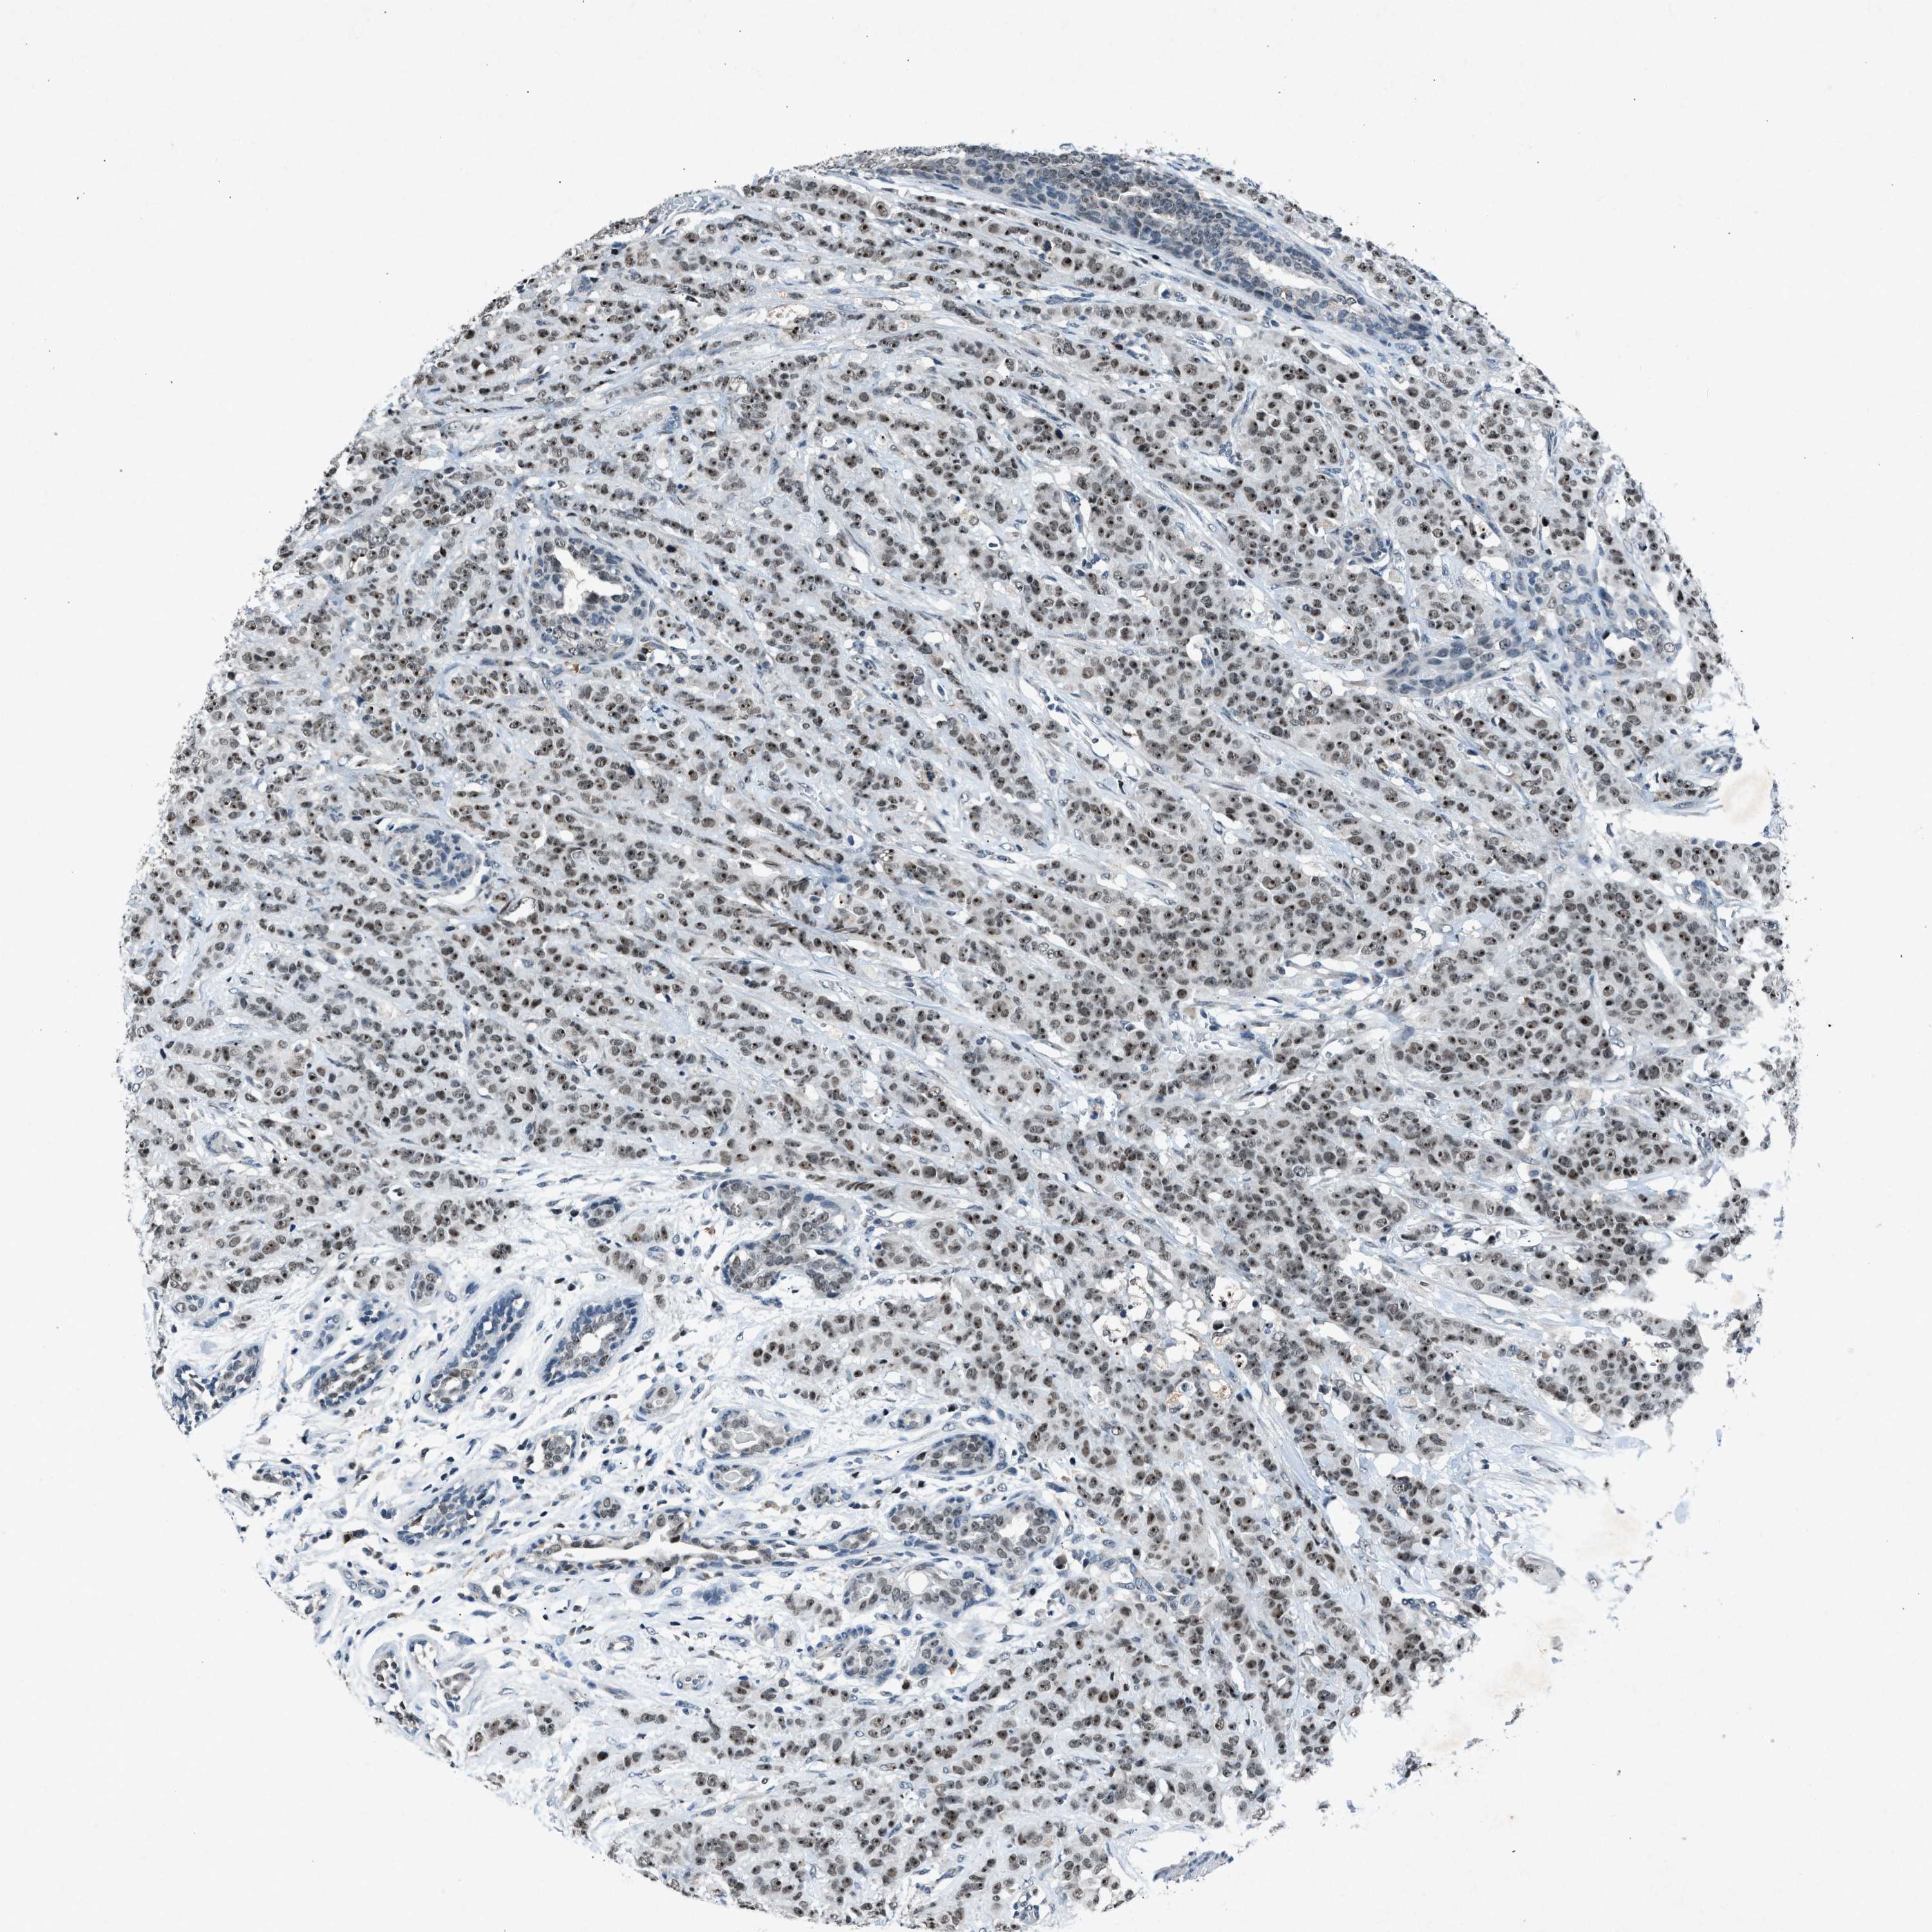

CANCER BREAST CANCER Show tissue menu

BRCA TCGA BRCA VALIDATION PROTEIN EXPRESSION